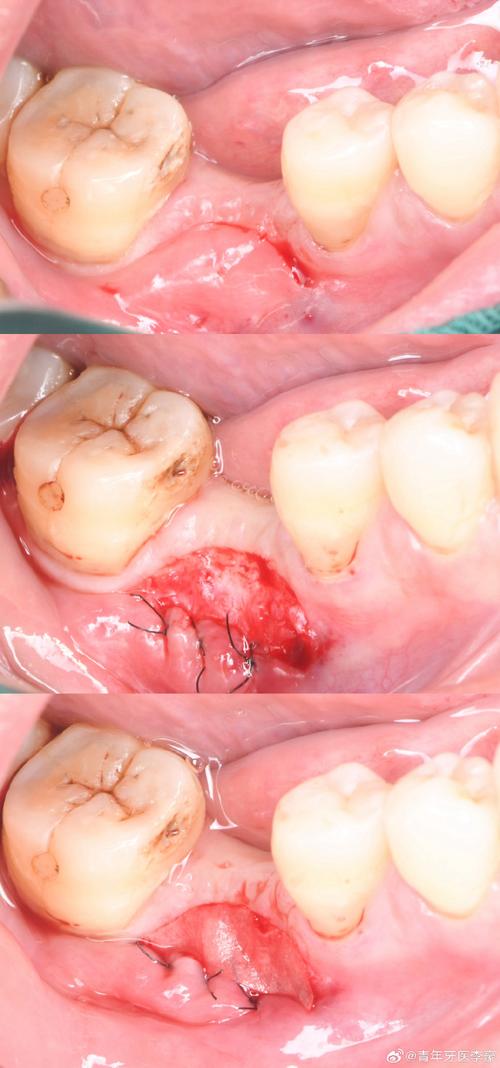

- 在缺牙区牙槽嵴顶做“梯形”或“弧形”切口,切开黏骨膜,翻瓣暴露骨缺损区域,彻底清除肉芽组织或炎性组织。

骨缺损处理与植骨

- 用球钻或超声骨刀修整骨缺损边缘,形成新鲜创面,促进骨细胞附着。

- 根据缺损大小选择合适植骨材料:若为颗粒状骨粉,可直接填入缺损区;若需支撑形态(如上颌窦提升),可配合使用骨胶原膜或钛网塑形。

屏障膜覆盖与缝合

- 将黏骨膜瓣复位,用可吸收缝线(如 Vicryl)严密缝合,关闭创口,避免植骨材料暴露。